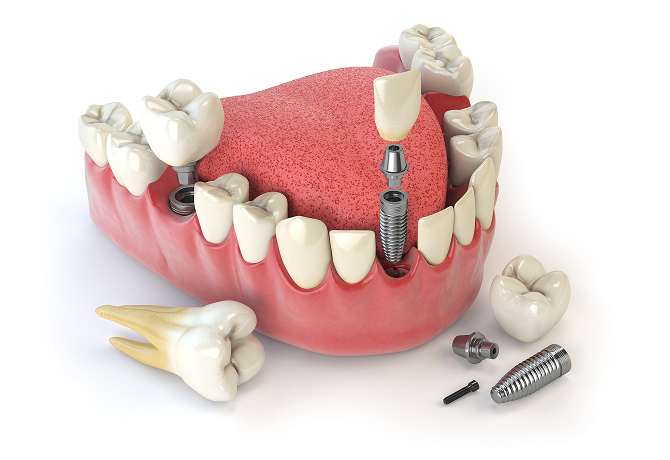

임플란트 치아 사진

보철물

실제 치아 역할을 하는

자연 치아 모양의 보철물입니다.

인공 치근

임플란트의 뿌리 역할로,

잇몸뼈에 식립합니다.

맞춤형 지대주

보철물을 지지하기 위해

인공 치근과 보철물을

연결하는 중간 구조물입니다.